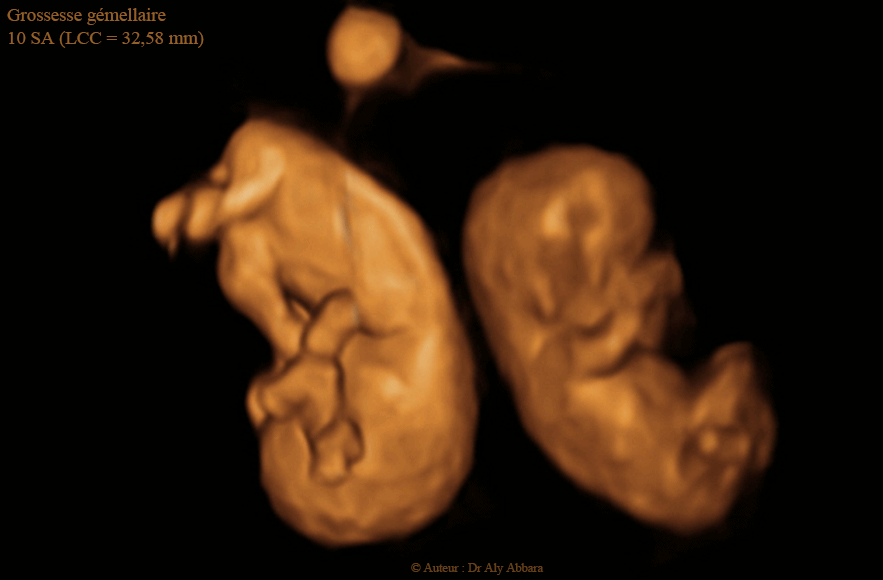

Vrais jumeaux dansant - 10 SA - توأمان حقيقيان بسن 10 أسابيع

Image échographique animée montrant deux jumeaux de 10 SA (LCC = 32.58 mm) ; il s'agit d'une grossesse gémellaire bi-amniotique monochoriale :

* Deux sacs amniotique (non visible sur ces images)

* Un seul chorion ; un placenta (non visible sur ces images)

* Deux vésicules ombilicales (une seule visible sur ces images)

A cet âge de grossesse, la conception passe du stade embryonnaire au stade fœtal, donc il s'agit de deux fœtus.